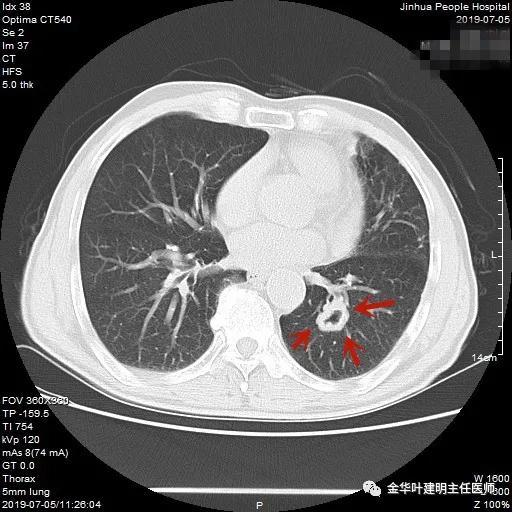

叶建明谈结节:检查发现肺实性结节怎么办?个人版实用指南

上图示鳞癌。病灶厚壁空洞,内壁凹凸不平,鳞癌可以乏收缩力,不一定有毛刺征或胸膜凹陷征。